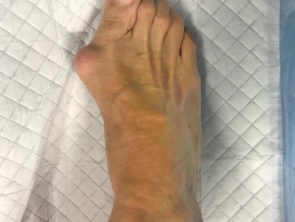

Диагноз – вальгусная деформация первого пальца правой стопы третьей степени (Hallux Valgus)

Проведена операция: двухуровневая корригирующая остеотомия с фиксацией интрамедуллярной (внутрикостной) спицей

Анестезия – спинальная

Длительность операции– 40 минут

Пациент отпущен домой в тот же день, период восстановления чуть больше месяца

После операции